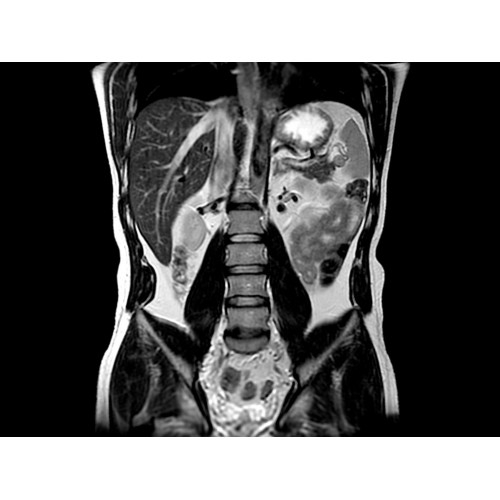

МРТ аппарат GE Optima MR450w 1.5T

МР-томограф с широким туннелем Optima MR450w является настоящей рабочей лошадкой и может эффективно обслуживать большее число пациентов. Томограф обеспечивает одновременно удобство пациента, продуктивность работы, отличное качество изображения. В этой МРТ-системе инженерам компании удалось без компромиссов совместить необходимый объем перемещения с удивительно высоким качеством изображения.

Благодаря принципиально новым технологиям мы расширили возможности МР-томографов с широкими туннелями, совместив непревзойденное качество изображений с высокой производительностью при широком — 50 см — поле зрения.

• Широкое поле зрения — поле зрения шириной 50 см позволяет охватывать крупные анатомические области за меньшее число сканов.